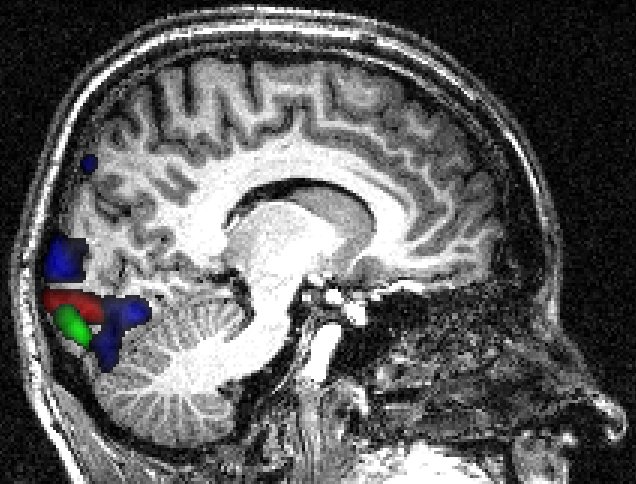

Retinotopic mapping of human visual cortex using fMRI is a well established method (Sereno et al. (1995); Warnking et al. (2002)) that allows to properly delineate low visual areas. It uses four separate experiments with 4 periodic stimuli (an expanding/contracting ring and a rotating counter or anti-counter clockwise wedge) to measure respectively eccentricity and polar angle maps. For this study, we only used functional MRI data corresponding to the expanding ring experiment (240 volumes acquired each 2 seconds). The periodic visual stimulus expanded from 0.2 to 3 degrees in the visual field during 32 seconds and was repeated fifteen times. This periodic stimulation generated a wave of activation in the retinotopic visual areas (Engel et al. (1994)), located in the occipital lobe, at the frequency of 1/32 Hz measured at a discrete temporal sampling of 2 seconds (equivalent to 1/16 temporal bins). After IC analysis of these functional data, using our R function \codef.icast.fmri.gui(), 18 and 15 components were automatically extracted respectively with tICA and sICA. In this experiment, we searched for components corresponding to cortical activation at the frequency of the visual stimulation. tICA and sICA extracted more (noisy) components than the ones specific to the stimulus. Indeed, the main problem with fMRI data is that each activated voxel of each volume contains a mixture of the signal of interest (BOLD effect) with several confound signals with several origins: ocular movement, heart rate, respiratory cycle, or head movement. Figure 10 shows the temporal and spatial components at the frequency of the visual stimulation corresponding to the cortical activation of interest. The computed phases are (approximatively) respectively equal to , and for tICA (green, red and blue components) and and for sICA (green and red components). Figure 10 displays on the corresponding anatomical image the cortical localization of these extracted components. For tICA and for each temporal component, this is done by selecting in the associated column of the estimated mixing matrix (see equation (4)) the most active voxels, defined arbitrarily (see Beckmann and Smith (2004) for another approach) as those whith a value above the 95% quantile (in absolute value). For sICA, we also thresholded arbitrarily each component at the 95% quantile. Based on the retinotopy property of the visual system, the expanding ring generates a cortical activation wave moving from the posterior part to the anterior part of the occipital lobe. As indicated in Figure 10 the computed phases of the extracted components increase as expected from the posterior to the anterior part of the occipital lobe.

![]() |

||

|||

As shown in Figure 12, the voxels containing the components extracted using temporal and spatial ICA were localized as expected in the same ventral cortical region, called V4-V8, known to be sensitive to color perception (Wade et al. (2002)).